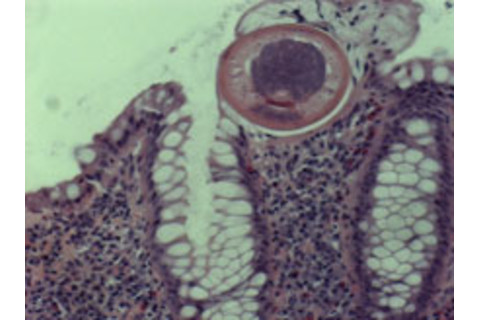

Inflamed areas of the man's colon weren't producing enough mucus, but where the worms were present, the colon was awash with it. Testing of the white blood cells in the worm-infested colon regions indicated that many of these immune cells had switched from producing interlukin-17, a protein which promotes inflammation, to interlukin-22, which promotes mucus production.

"Ulcerative colitis is often associated with decreased mucus production and the worms seem to somehow restore mucus production.... It's possible the mucus serves as a defensive barrier between bacteria and the gut that prevents bacteria from causing inflammation and crossing over into other tissues."